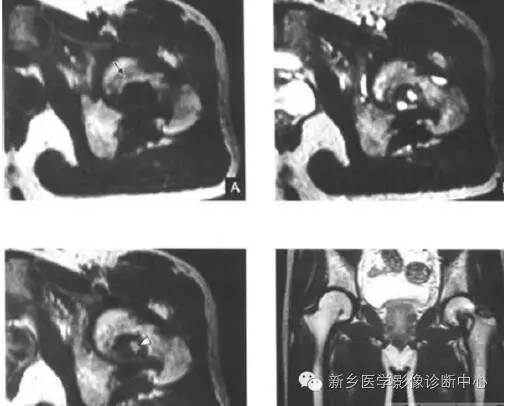

甲状旁腺机能亢进之棕色瘤

甲状旁腺功能亢进称甲旁亢,是由于甲状旁腺分泌过多的甲状旁腺素,引起钙、磷代谢失常的疾病,具有多种临床,但仅有部分病人发生骨骼改变生化检查可见血清钙增高,血清磷下降,碱性磷酸酶增高原因为甲状旁腺腺瘤或癌,甲状旁腺增生骨骼改变包括:骨质疏松,骨外膜下骨皮质吸收,局限骨质破坏等。

影像表现(棕色瘤)

局限性囊状骨破坏,表现为大小不一、单个或多发的囊状透光区,与周围骨质边界清楚,较大者可向外膨胀,有时可呈多房皂泡样改变,类似巨细胞瘤,多见于长骨和下颌骨。这种单房或多房样的囊状破坏临床又称为棕色瘤,于手术切除腺瘤后,可在短期内修复。较大的棕色瘤常伴发病理骨折。

读片要点:1、好发任何年龄,女性多见2、好发骨盆、长骨、颌骨3、长骨可变形,骨端不增宽,可伴骨折4、生化检查可见血清钙增高,血清磷下降,碱性磷酸酶增高